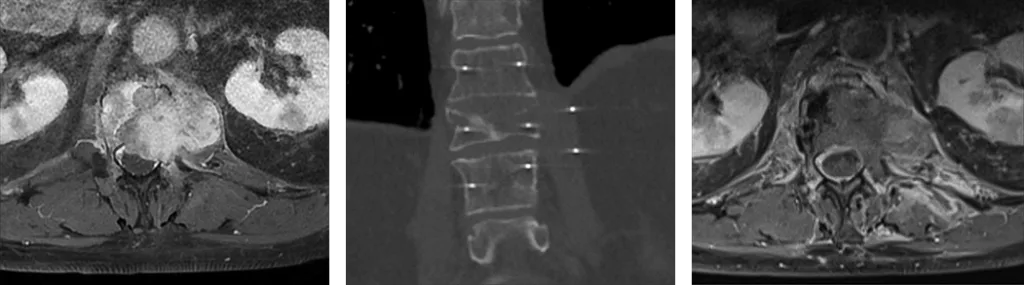

Figure 3 : Métastase vertébrale avec atteinte épidurale responsable d’une compression médullaire, progressive après radiothérapie. Traitement par électrochimiothérapie permettant une bonne réponse locale (décompression médullaire)